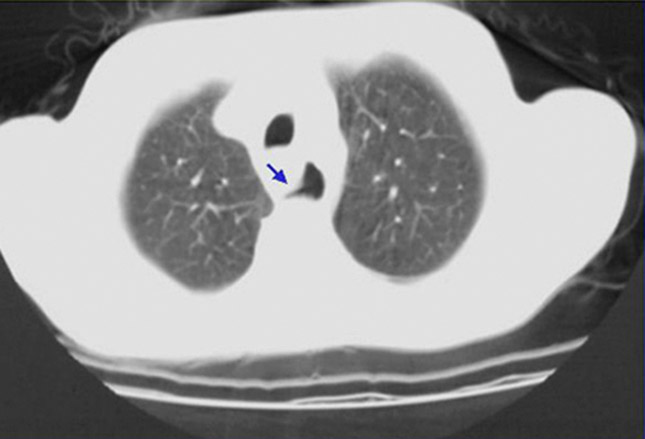

X线片可显示胆囊壁内空气,可经CT成像确认(如图)。气肿性胆囊炎是外科急症,有15%-20%的死亡率。

前图胸片显示泛影葡胺

对比材料泄露(短箭头)进入胸膜腔的左后外侧,说明食管穿孔(指向胃管的长、细箭头)。左侧胸腔积液

是布尔哈夫综合征患者最常见的影像学表现。这种综合征的疼痛通常是剧烈的,严重的,并且弥漫于腹部到颈部的所有位置。患者可以快速发生心动过速,呼吸急促及低血压,导致休克。也可发生纵隔炎;胸部听诊,能听到“Hamman crunch”(一种噼里啪啦的声音,与每次心跳相符合)。胸部CT研究通常能确定布尔哈夫综合征的诊断;也可能显示起源于食管的错误通道(箭头)。